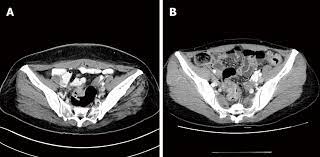

The Radiology Assistant Endometriosis Mri Detection from radiologyassistant.nl B, ct scan shows a nonspecific mass involving the right rectus muscle (arrow) subsequently proven to be endometriosis. After taking your medical and symptom history, and after performing a pelvic exam, your provider may recommend imaging. A ct or mri may show the endometriosis. Unusual sites of implantation and associated complications may make. Ct, endometriosis, female pelvis, mri, ultrasound. Endometriosis is a painful condition in which tissue that normally lines your uterus (endometrial tissue) grows in other parts of your pelvis, such as your ovaries or fallopian tubes. It can get worse before and during your period. An ultrasound, a ct scan, or an mri can make detailed pictures of your organs.

Cureus Appendicitis Caused By Endometriosis Within The Bowel Wall from assets.cureus.com Plain film radiography, computed tomography (ct) scanning, and barium studies are not sensitive for the diagnosis of endometriosis. Detection and localization of deep endometriosis by means of mri and correlation with the enzian score. The most common symptom is pelvic pain. Ct hrct is the modality of choice for thoracic endometriosis, which may demonstrate presence of pneumothorax, hemothorax or nodules which may change in nature cyclically. Tell the healthcare provider if you have ever had an allergic reaction to contrast liquid. A ct or mri may show the endometriosis. This type of endometriosis is called, deeply infiltrating or deeply infiltrative endometriosis die because it is found deep within the tissue or organ. Endometriosis is a condition in which the inner lining of the uterus (endometrium) grows outside the uterus in locations such as the fallopian tubes, ovaries, bladder, or other structures in the pelvis, causing pain, irregular bleeding, and possible infertility

The most common symptom is pelvic pain. Plain film radiography, computed tomography (ct) scanning, and barium studies are not sensitive for the diagnosis of endometriosis. This type of endometriosis is called, deeply infiltrating or deeply infiltrative endometriosis die because it is found deep within the tissue or organ. Endometriosis is an important cause of chronic pelvic pain and infertility. The most common symptom of thoracic endometriosis is chest pain occurring right before or during menstruation. To diagnose endometriosis in the bowel, a physician conducts an examination that includes a vaginal examination, ultrasound, and a ct or mri scan. You may be given contrast liquid to help your abdomen show up better in the pictures. Tell the healthcare provider if you have ever had an allergic reaction to contrast liquid. Endometriosis is derived from the word endometrium, which is the tissue that lines the uterus. Endometriosis is defined as the presence of endometrial glandular and/or stromal cells outside of the uterine cavity. Learn about treatment, causes, stages, surgery, and diagnosis. The ct and mr characteristics of abdominal wall endometriosis are nonspecific, both showing a solid enhancing mass in the abdominal wall. The most common sign of endometriosis is pain in your lower belly that doesn't go away.